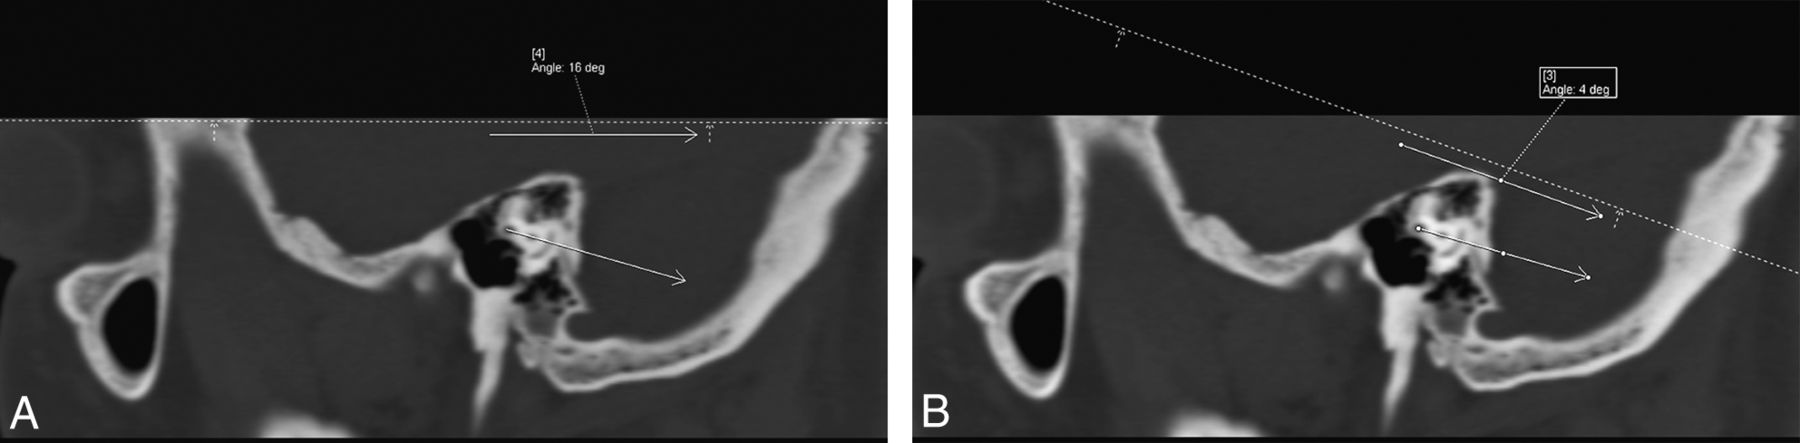

The difference in the angle between the axial reformat plane and the plane of the lateral semicircular canal was measured by the neuroradiology trainee and confirmed as accurate by the senior neuroradiologist. This angle difference is hereafter termed the “error angle.” The error angle was measured by generating sagittal images and then using an electronic angle-measurement tool, drawing a first line along the dashed axial image cross-reference line followed by a second line through the anterior and posterior limbs of the lateral semicircular canal (Fig 2). Sagittal images were generated and angles were measured with the postprocessing software of our department (syngo.via; Siemens, Erlangen, Germany).

A 55-year-old woman with a normal left temporal bone. Sagittal noncontrast CT images in bone windows at the same location demonstrate the method of measuring the axial plane error angle. A, The angle between a line drawn by a radiologist at a PACS workstation through the anterior and posterior limbs of the lateral semicircular canal and a line drawn parallel to the plane chosen by the automation software (dotted line), which, in this case, is very close to the acquisition plane, is 16°. B, The angle between a line drawn by a radiologist at a PACS workstation through the anterior and posterior limbs of the lateral semicircular canal and a line drawn parallel to the plane selected by the technologist (dotted line) at the CT console is 4°.